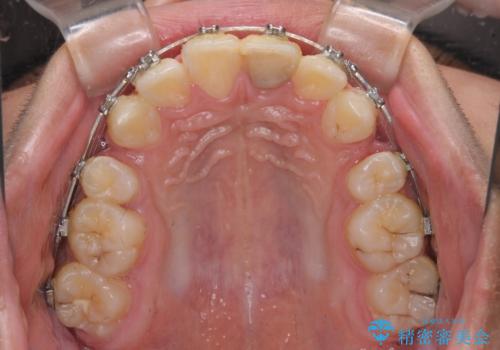

膨らんだ口元 ワイヤー装置での抜歯矯正

- メタルブラケット

上下前歯が著しく前突している状態であったので、上下左右の第1小臼歯4本を抜歯し、ワイヤー装置にて矯正治療を行うこととしました。